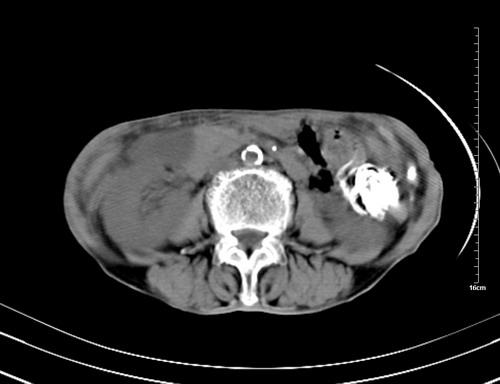

病人,女,79岁,主要因腹疼二月入院,彩超,肝,胆,脾,未见异常,胸透上消化道造影未见异常,化验白细胞增高,内科医生让做胸部ct检查,因为熟人多做了腹部(外科会诊考虑胆囊炎).现ct片如下请假各位战友.

1 气管旁、隆突下淋巴结明显肿大,肝左叶外侧段低密影,都考虑转移。

2 肝右后叶下段明显增大,片状低密影,但因各种伪影显示不佳,不排除病变。

后中纵隔团块影,伴气管、食道受压移位,首先考虑转移瘤,肝s5段低密度灶。建议增强检查,另外其结肠是否有问题请提供,右肺部分肺叶局限含气增多,考虑局限肺气肿。

后中纵隔团块影,伴气管、食道受压移位,首先考虑转移瘤,肝表现同11773。